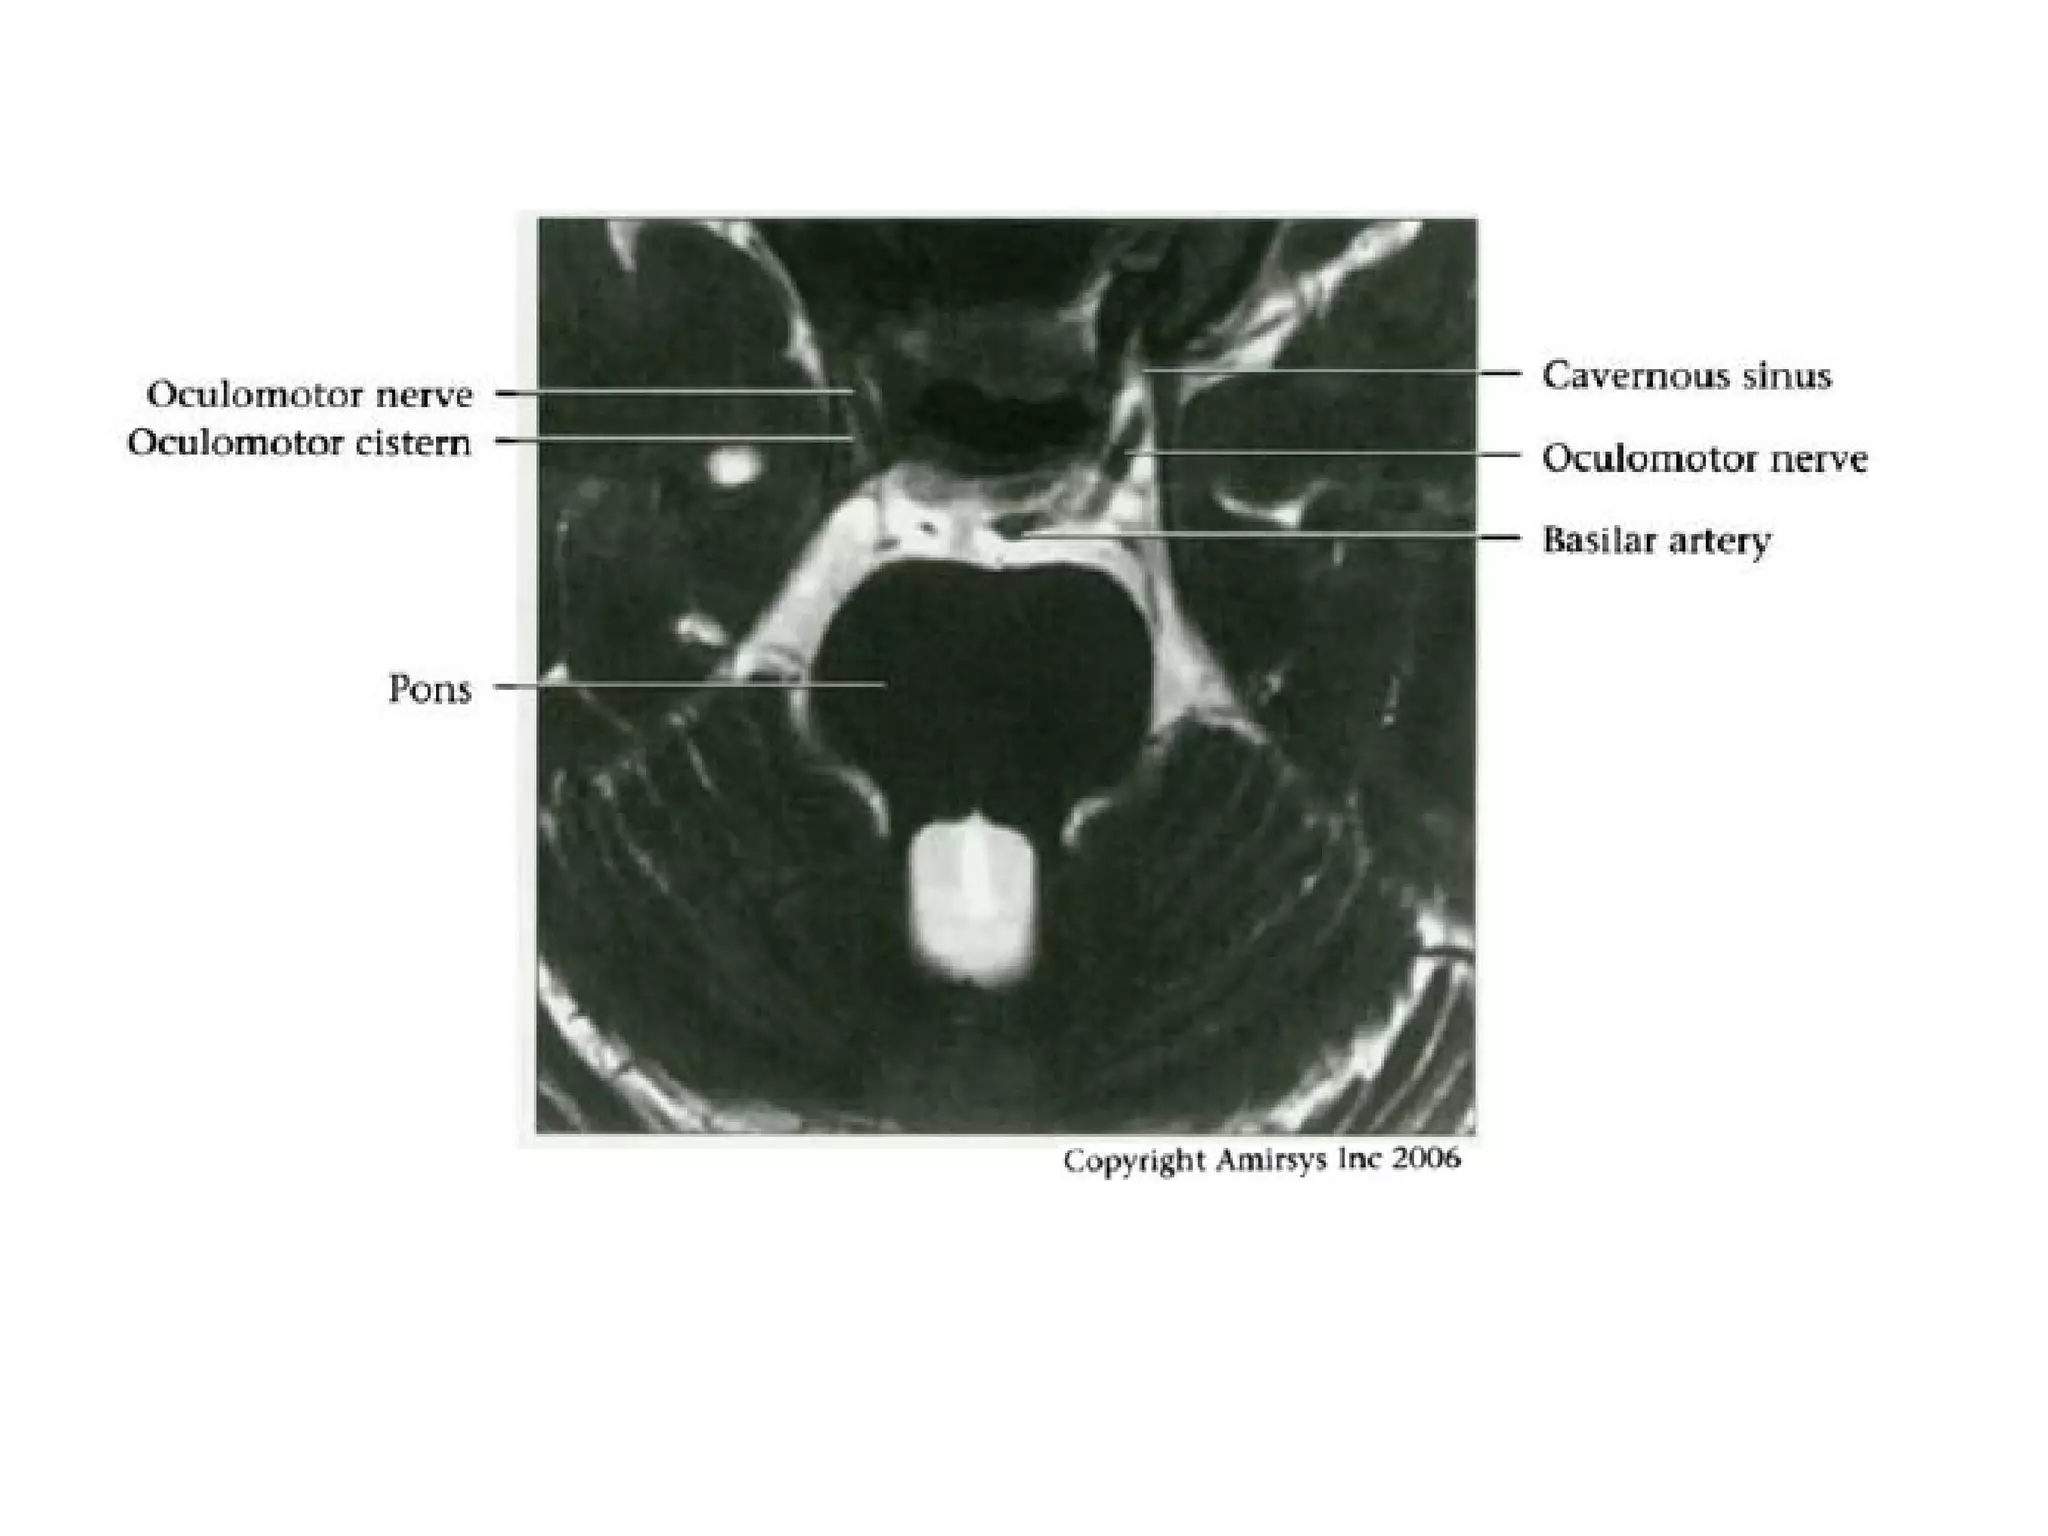

Cranial Nerve III:

The Oculomotor Nerve

• The oculomotor nerve originates from nuclei deep to the

superior colliculus, ventral to the cerebral aqueduct, and

inferior to the pineal gland.

• The nerve then travels across the midbrain from

posterior to anterior.

• The oculomotor nerve root emerges into the

interpeduncular cistern, and this root entry zone in the

cistern is a good way to identify the oculomotor nerve on

axial SSFP MR images.

• In the prepontine cistern, the nerve travels between the

superior cerebellar and posterior cerebral arteries, which

makes it easy to identify on coronal SSFP images.

• The cavernous segment of the oculomotor nerve

runs along the lateral wall of the cavernous sinus

and is the most superior of the nerves in this

sinus.

• The oculomotor nerve then enters the orbit

through the superior orbital fissure, before

splitting into superior and inferior divisions lateral

to the optic nerve.

• Knowledge of this anatomy may be helpful for

identifying the precise location of a nerve

abnormality.

RadioGraphics 2009; 29:1045–1055